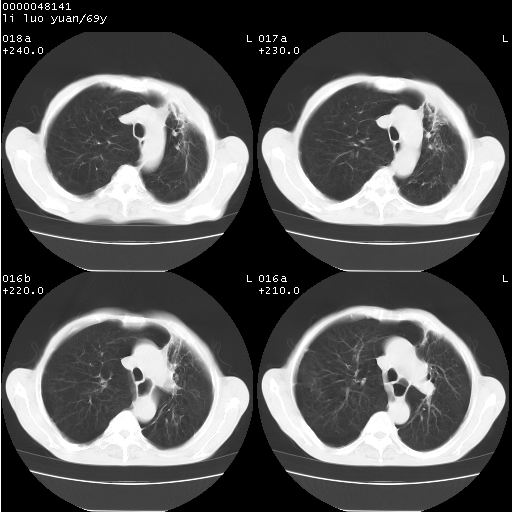

临床资料:老年患者,咯血、消瘦

影像表现:桶状胸,双肺纹理纤细、紊乱,透过度增高,肺野内可见多发、散在、大小不等的无壁高透过影,右肺中叶外侧段分叶样软组织占位,左上肺纤维索条样密度影,相应层面左侧胸腔轻度萎陷,纵隔左移。

影像诊断:1、慢支、肺气肿、双下肺野肺大泡形成

2、左上肺陈旧性肺结核

3、右肺中叶外侧段占位 考虑肺ca可能性较大、建议增强及痰检脱落细胞